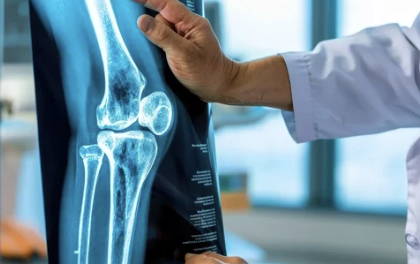

무릎에 물이 차는 증상(관절삼출): 원인부터 치료 및 예방법까지

무릎 관절에 물이 차는 증상은 관절삼출(Joint Effusion) 또는 무릎 부종(Knee Effusion)이라고 하며, 이는 관절 내에 과도한 활액(관절액)이 축적되는 현상을 의미합니다. 무릎 관절은 원활한 움직임을 돕기 위해 소량의 관절액을 유지하지만, 염증, 부상, 질환 등의 원인으로 인해 비정상적으로 많은 양의 액체가 축적되면서 붓고 통증이 발생할 수 있습니다.

| X-ray 검사 | 무릎 관절의 골절, 뼈의 이상 여부 확인 |